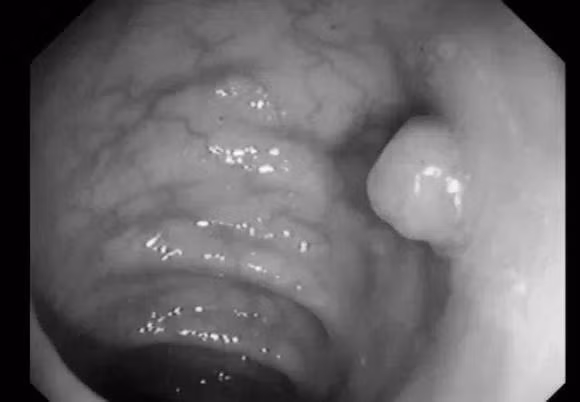

"Phần còn lại" của polyp thực sự có nghĩa là dư thừa, đó là phần thực vật thừa trên niêm mạc ở bề mặt bên trong của ruột. Trên thực tế, nó là một "vết sưng thịt" trên bề mặt niêm mạc ruột già.

Nói một cách chính xác, polyp đại trực tràng là những tổn thương nhô cao từ bề mặt niêm mạc ruột đến khoang ruột, đây là bệnh thường gặp, hơn 70% trong số đó là polyp tuyến.

Polyp đường ruột